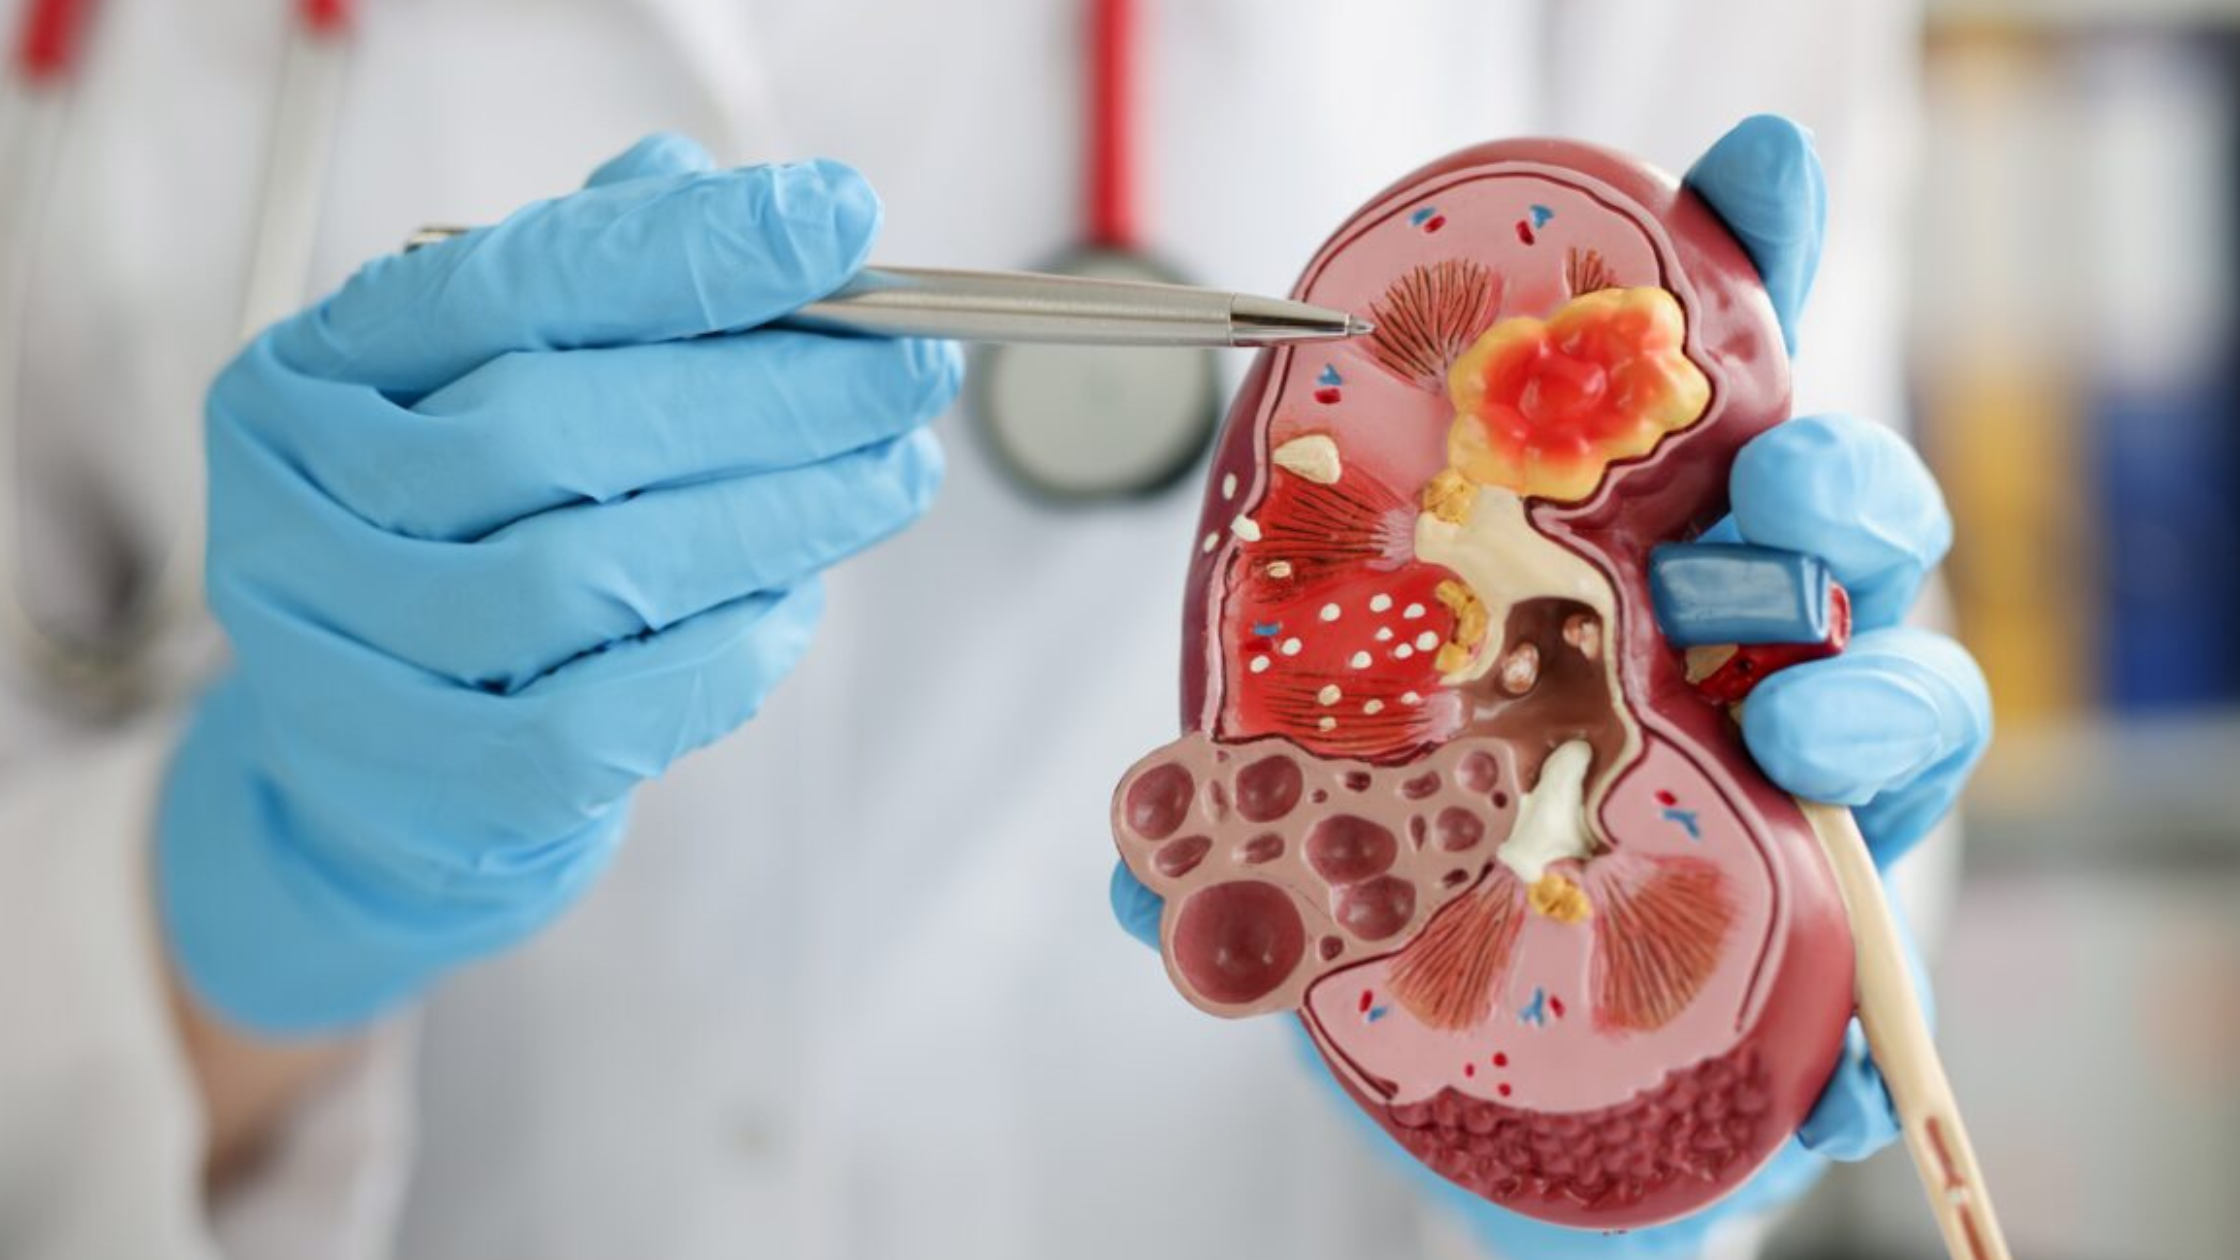

Kidney stones can bring about excruciating pain and discomfort, affecting millions of individuals globally. When these stubborn stones refuse to pass naturally or grow too large to be managed with […]